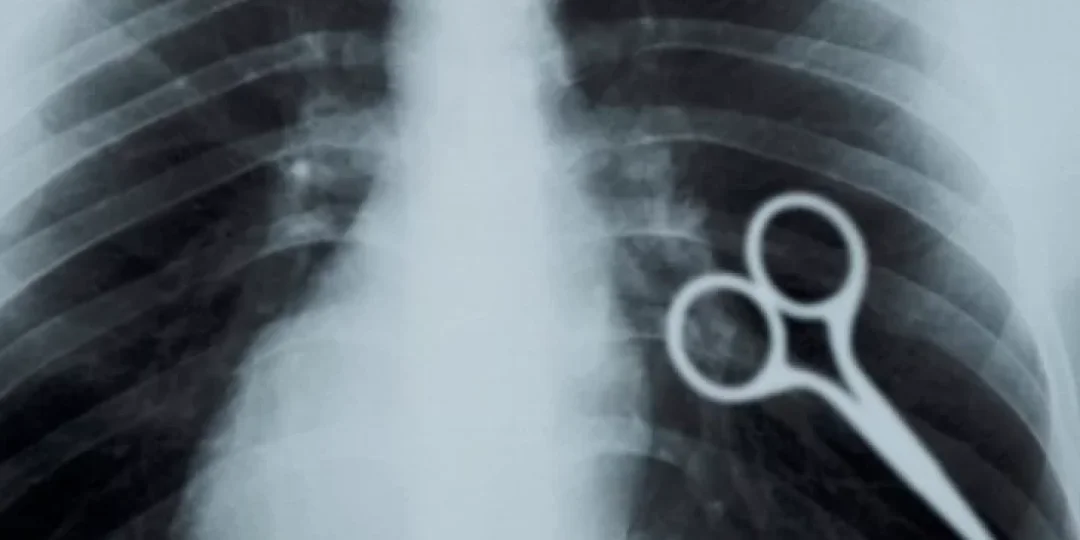

Un insólito incidente ocurrió el lunes por la noche en el penal de Chimbas (San Juan), donde Axel Hernán Rojas, un recluso condenado por delitos contra la propiedad, sorprendió a las autoridades al tragarse la mitad de una tijera en lo que, aparentemente, fue un acto de protesta.

A pesar de la negativa de Rojas a recibir atención médica en un principio, las autoridades penitenciarias actuaron con rapidez para evitar complicaciones mayores. En cuestión de horas, el juez de Ejecución penal, Federico Zapata, autorizó el traslado de Rojas a un hospital, donde el personal médico pudo intervenir. Afortunadamente, no fue necesaria una cirugía, ya que el interno logró expulsar el objeto por sus propios medios, y su estado de salud es estable. Actualmente, se encuentra fuera de peligro.